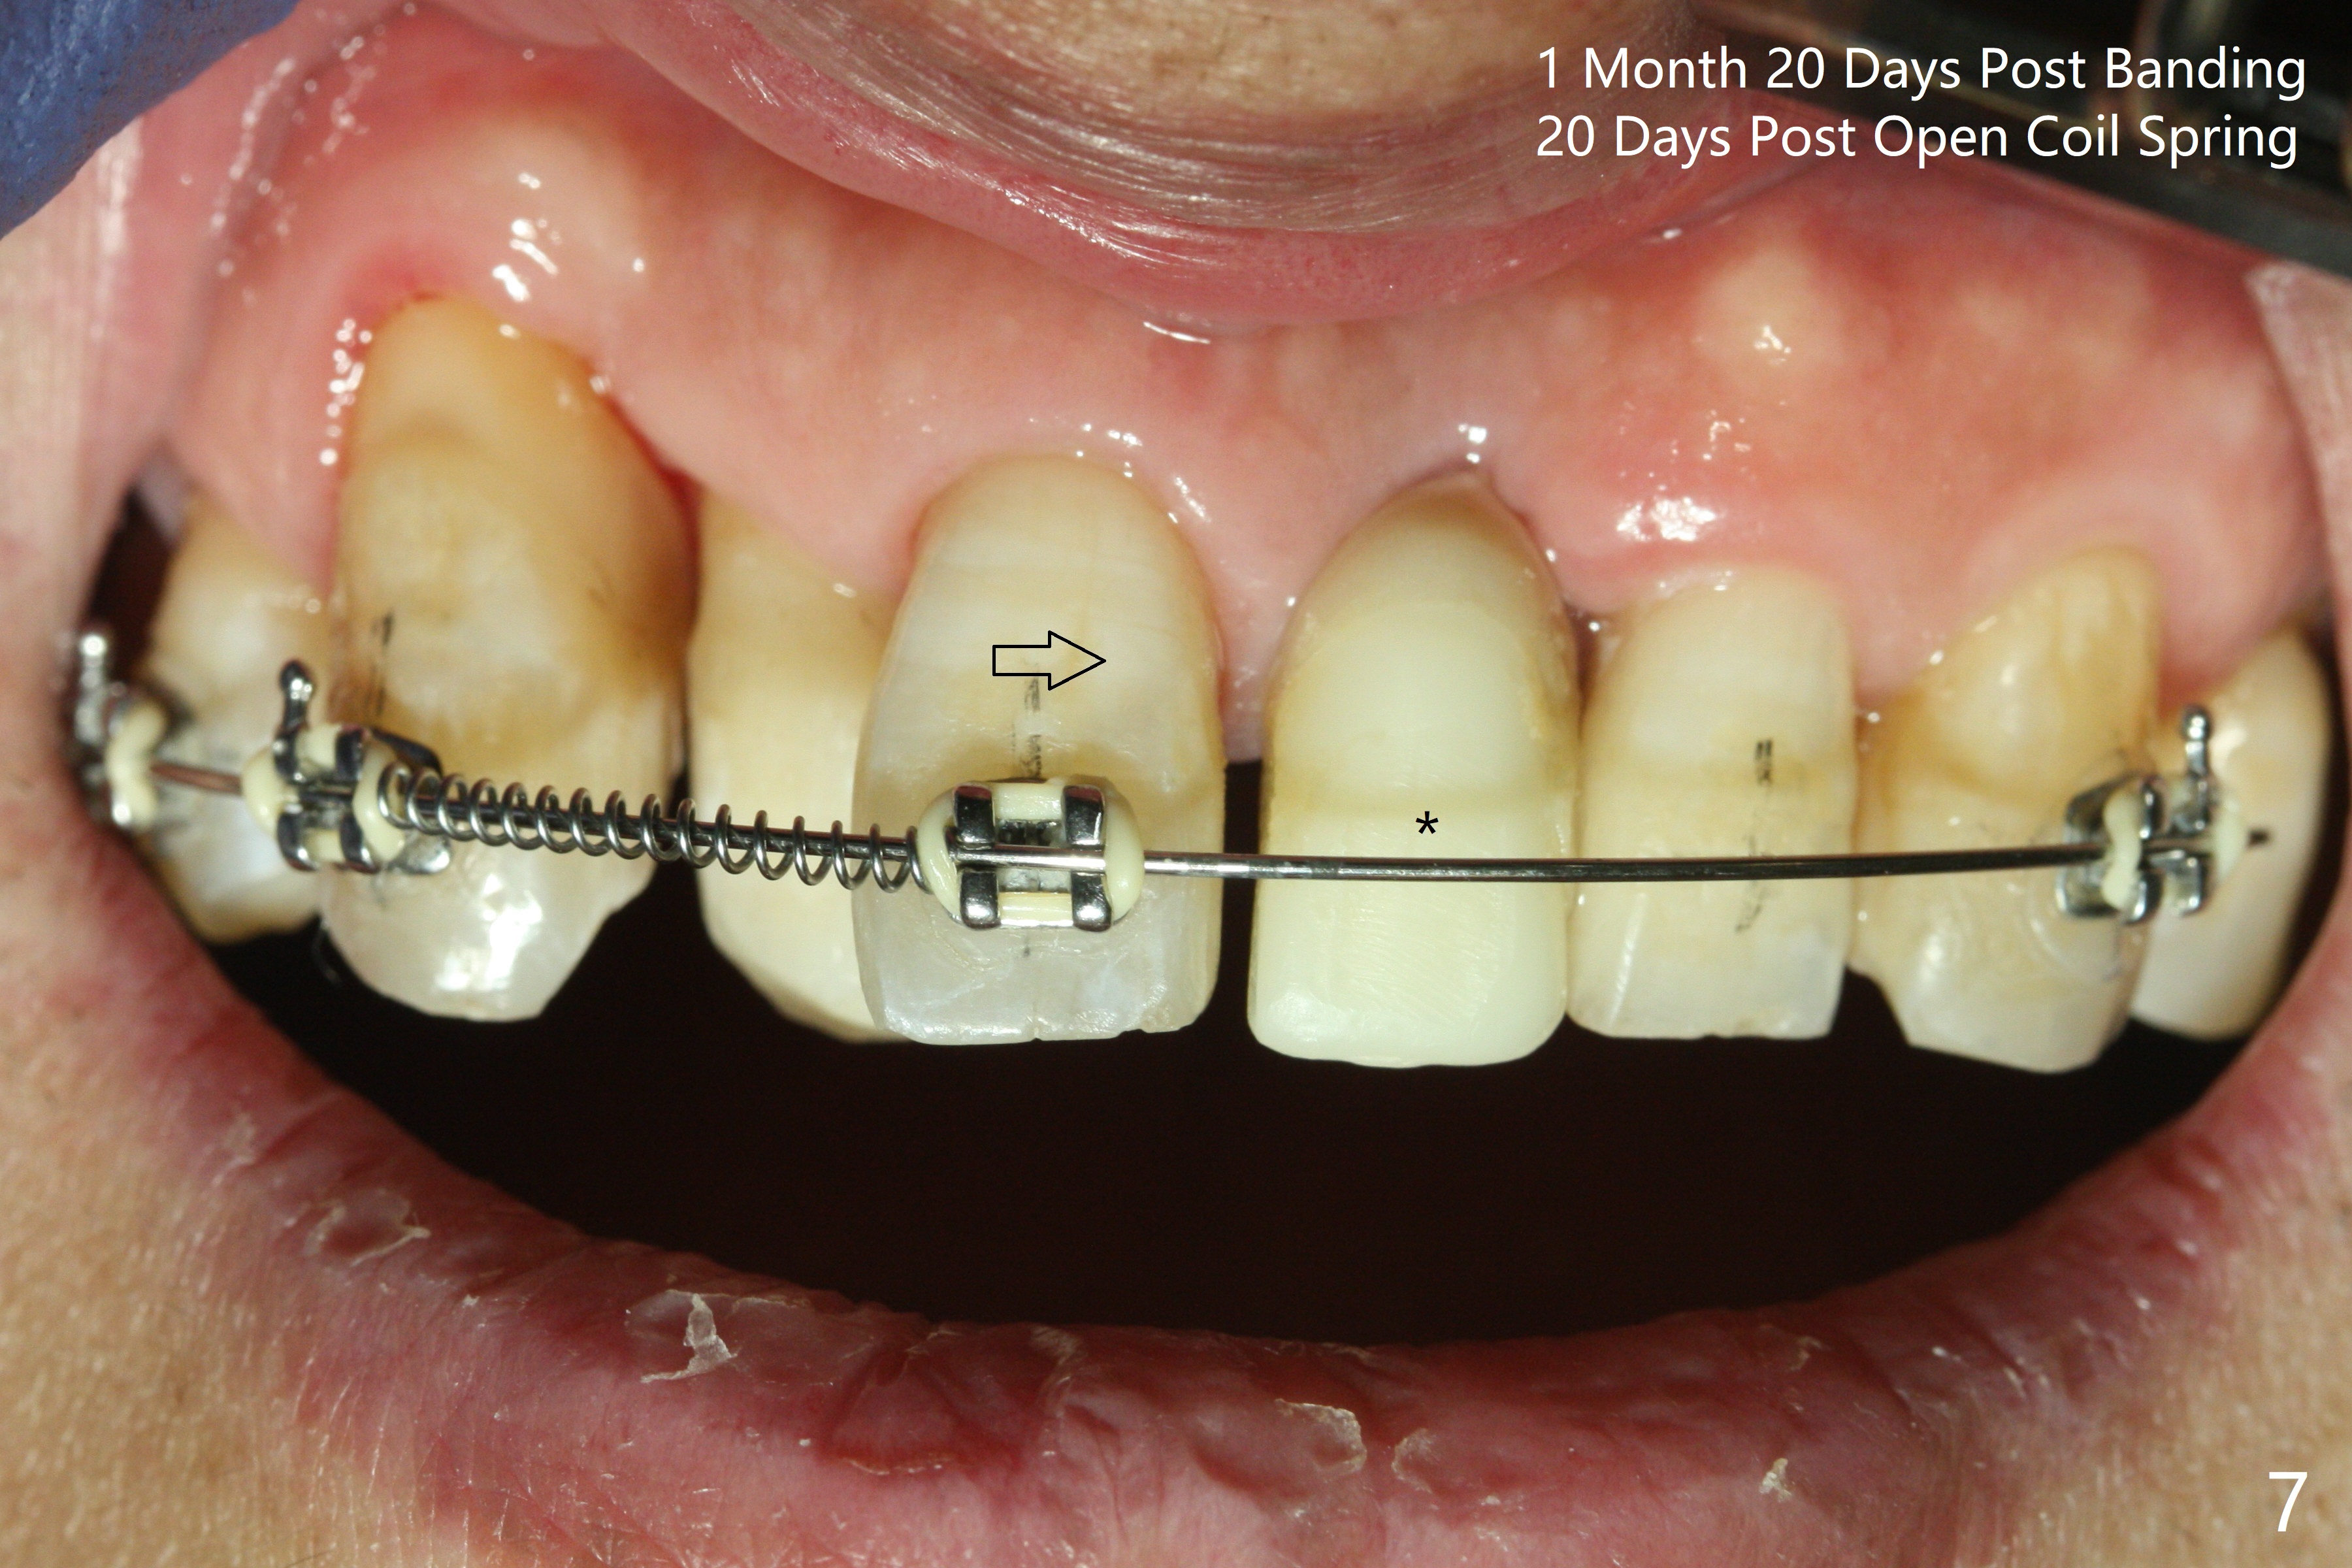

Reduction